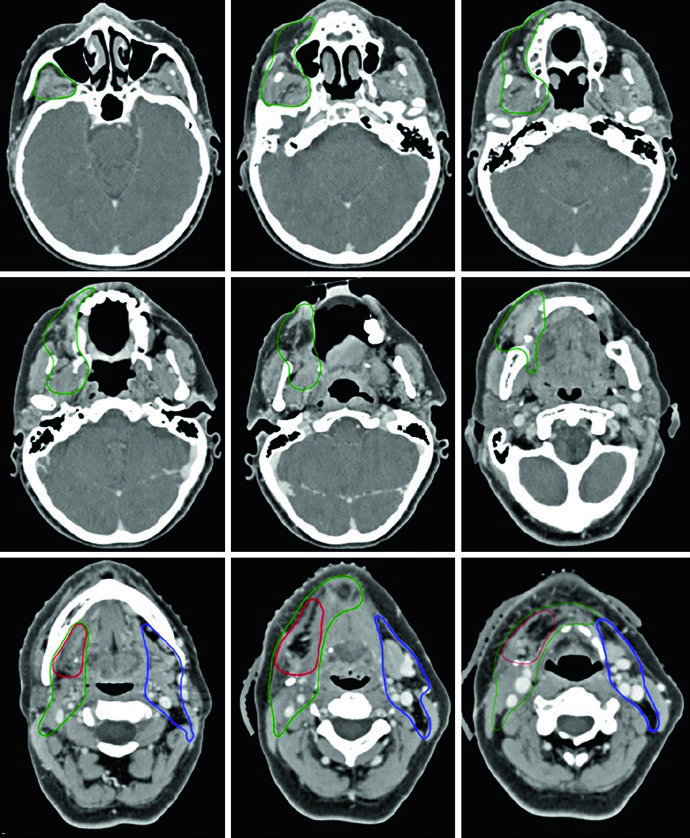

Caso Clínico: Carcinoma de Lengua Oral T3N2b

La Figura 6.1 ilustra un paciente con carcinoma espinocelular (CEC) de lengua oral, estadio patológico T3N2b, post-glosectomía parcial con márgenes quirúrgicos microscópicamente positivos. El CTV66 (rojo) cubre la región del margen positivo. El CTV60 (verde) abarca todo el lecho quirúrgico, y el CTV54 (azul) incluye los niveles ganglionares cervicales.

En el lado ipsilateral se incluyen los niveles I a V. En el contralateral sin enfermedad, niveles I a IV. La cobertura del nivel V se recomienda para tumores primarios de lengua oral, especialmente tras manipulación quirúrgica del cuello y en presencia de enfermedad ganglionar ipsilateral. El nivel IA debe cubrirse sistemáticamente.

Cuando existe preocupación por compromiso de tejidos blandos superficiales, se recomiendan bolus y flash. El espacio retroestiloideo ipsilateral es zona de riesgo para metástasis ganglionar, particularmente con compromiso del nivel II. Los ganglios retrofaríngeos presentan bajo riesgo y generalmente no se incluyen. La cobertura del nivel VI se recomienda enfáticamente en pacientes con enfermedad ganglionar positiva.